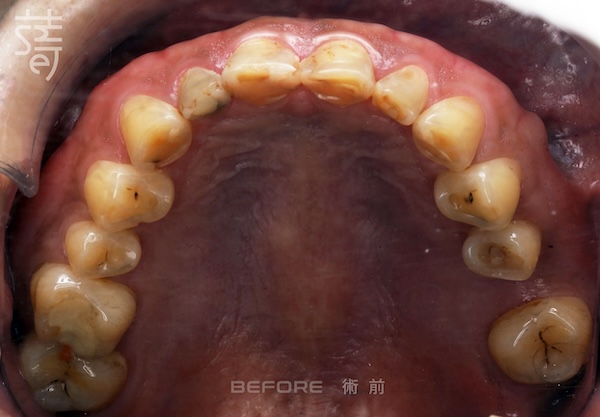

薛聖儒醫師為李先生規劃了三大治療階段,從齒列矯正、重建後牙支撐,到全口美學修復,以循序漸進的方式調整咬合高度,讓功能與外觀同步回歸理想狀態。

Dr. Xue mapped out three treatment stages for Mr. Li: teeth alignment, restoring molar support, and full-mouth aesthetic reconstruction. Each phase progressively adjusted the bite height, bringing function and appearance back into harmony.

最後進行全口假牙與美學修復。許多人以為這一步只是追求美觀,其實這正是確保牙齒能長期穩定的關鍵步驟,讓美觀與功能同時回歸理想。

Finally, full-mouth prosthetics and aesthetic restoration were completed. Many assume this step is purely cosmetic, but it’s actually crucial for long-term stability.